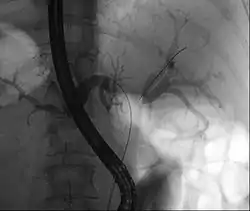

![]() ورم كلاتسكين خلال تصوير البنكرياس والأقنية الصفراوية بالتنظير الباطني بالطريق الراجع ورم كلاتسكين خلال تصوير البنكرياس والأقنية الصفراوية بالتنظير الباطني بالطريق الراجع | |